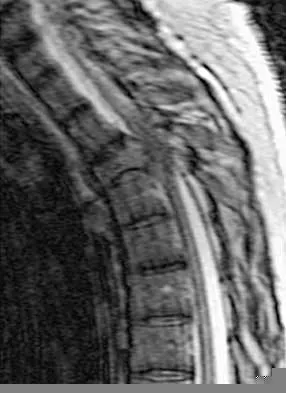

A 73-year-old woman reports a 4-month history of severe left-sided posterior buttock pain and left leg pain. The leg pain radiates into the left lateral thigh and posterior calf with cramping. Examination reveals mild difficulty with a single-leg toe raise on the left side and a diminished ankle reflex. There is also a significant straight leg raise test at 45 degrees which exacerbates symptoms. An MRI scan is shown in Figure 4. What is the most appropriate treatment at this time?

Lumbar spinal stenosis with lumbar radiculopathy can be commonly caused by a synovial cyst arising from the facet joints. Lyons and associates reported on the surgical treatment of synovial cysts in 194 patients. Of the 147 with follow-up data, 91% reported good pain relief and 82% had improvement of their motor deficits. Epstein reported a 58% to 63% incidence of good/excellent results and a 38 to 42 point improvement on the SF-36 Physical Function Scale. It was also suggested that since the presence of a synovial cyst indicates facet pathology, possible fusion should be considered in these patients, especially those with underlying spondylolisthesis. Lyons MK, Atkinson JL, Wharen RE, et al: Surgical evaluation and management of lumbar synovial cysts: The Mayo Clinic Experience. J Neurosurg 2000;93:53-57. Khan AM, Synnot K, Cammisa FP, et al: Lumbar synovial cysts of the spine: An evaluation of surgical outcome. J Spinal Disord Tech 2005;18:127-131.

A 60-year-old woman with a history of breast cancer has progressive paraparesis. The MRI scan is shown in Figure 28. What form of management is most likely to restore or maintain ambulation?

Surgical decompression and stabilization have been shown to be the most effective means of improving neurologic function. Decompression is most reliably done from the side of the compression, which is anterior in this patient. Harrington KD: Metastatic tumors of the spine: Diagnosis and treatment. J Am Acad Orthop Surg 1993;1:76-86.

A 65-year-old man with ankylosing spondylitis sustains an extension injury to his cervical spine. Two days later, a progressive neurologic deficit develops at the C6 level. An MRI scan is shown in Figure 1. What is the most likely diagnosis?

It is common for patients with ankylosing spondylitis to sustain extension-type fractures, typically near the cervicothoracic junction. These fractures can be minimally displaced, making them difficult to diagnose. In addition, the vertebral bodies are vascular and their canals are relatively enclosed, making them vulnerable to epidural bleeding. The MRI scan shows an epidural hematoma posteriorly compressing the cord. Bohlman HH: Acute fractures and dislocations of the cervical spine. J Bone Joint Surg Am 1979;61:1119-1142. Weinstein PR, Karpman RR, Gall EP, et al: Spinal cord injury, spine fracture and spinal stenosis in ankylosing spondylitis. J Neurosurg 1982;57:609-616.